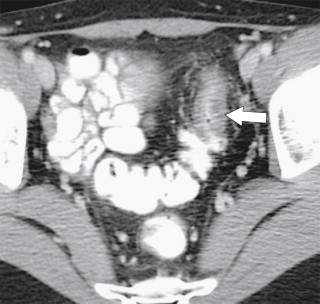

In addition to perforation from toxic megacolon, the greatest risk to patients with chronic UC is the late development of adenocarcinoma of the colon, for which they have an increased risk of 5% to 30% over the general population ( Fig. 5-18 ). The risk increases by 10% for each decade of disease. Patients with more extensive disease may therefore undergo prophylactic colectomy.

Figure 5-18, Axial ( A ) and coronal ( B ) contrast-enhanced CT in a 61-year-old woman with known ulcerative colitis and now an ascending colon adenocarcinoma ( arrows ) with associated lymphadenopathy ( small arrow ).